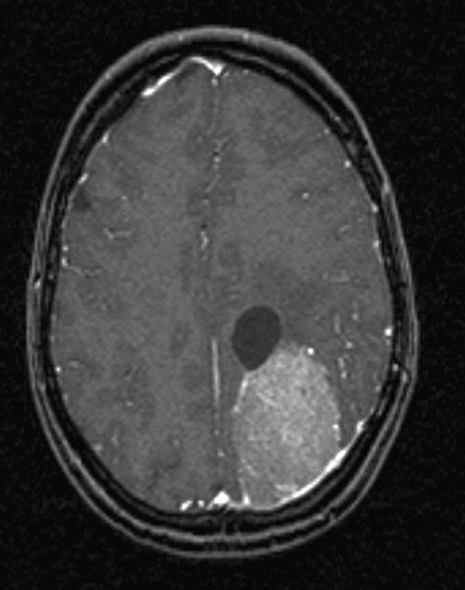

Hjerne, Meningeom med cyste, MR

MR-skanning af hovedet med kontraststof viser et bredbaseret meningeom med kraftig kontraststof-opladning. Der er yderligere en cyste ved siden af meningeomet.

Gengivet med tilladelse fra Radiologisk afdeling, Universitetssygehuset Nord-Norge